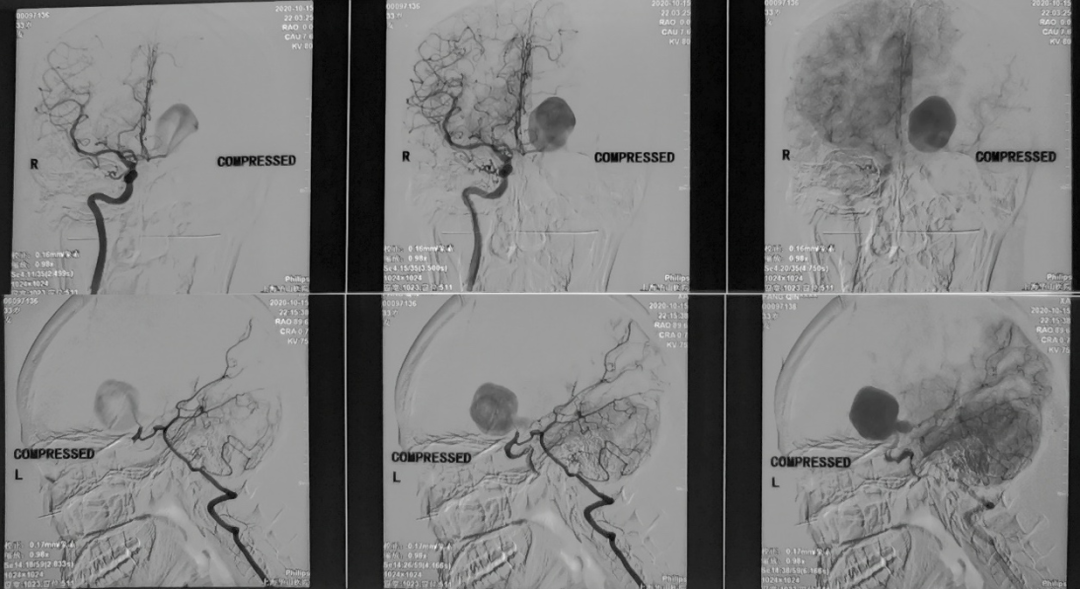

术中电生理未见明显异常,因此未进行进一步血流重建处理。